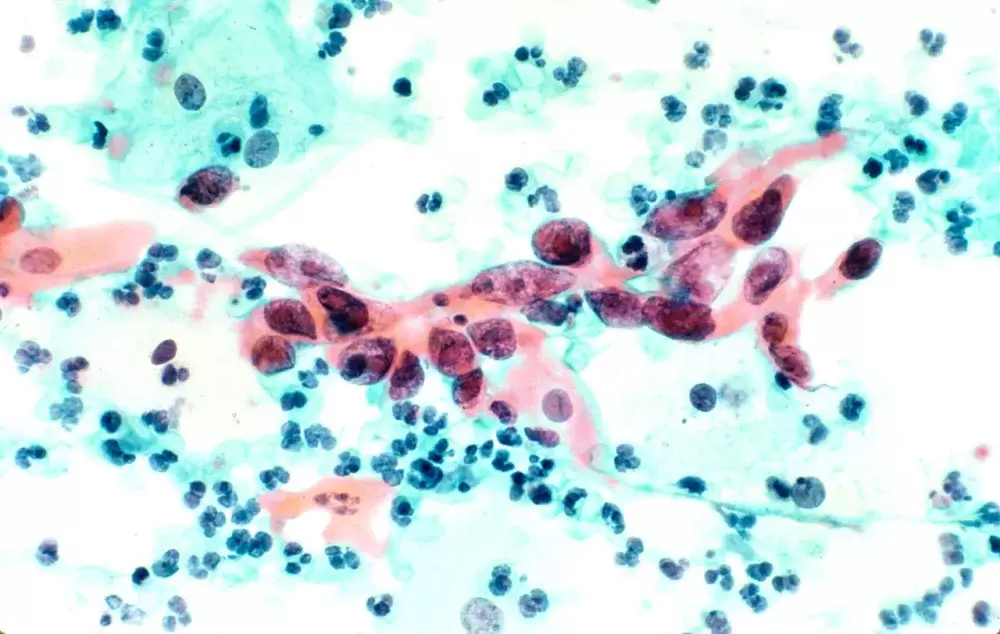

This May the FNHA launched the Screen. For Wellness campaign, a messaging initiative that stresses the importance of early cancer detection for the province’s First Nations peoples. The campaign focuses on breast, cervical and colorectal cancer, which were identified as the most common forms of the disease in a joint study published by the FNHA and BC Cancer in September 2017. To promote early detection, Screen. For Wellness encourages women over 40 to get a mammogram, even if they have no symptoms of breast cancer, while females aged 25 to 69 who have a cervix should regularly get a Pap test in case cervical cancer is present. The campaign also encourages women and men between 50 and 74 to screen for colon cancer, regardless of their lack of symptoms.

Cancer is the leading cause of death in Canada, and two in five people will have the disease at some point in their lifetime, according the Canadian Cancer Society. In B.C., breast cancer is the most common form found in First Nations women, while prostate and colorectal have the highest rates of incidence among Aboriginal men, according to 2017 cancer study. Cervical cancer was also found to be 92 per cent more common in First Nations women than other females in B.C., while colorectal cancer was 39 per cent more likely to affect Indigenous men than other males.